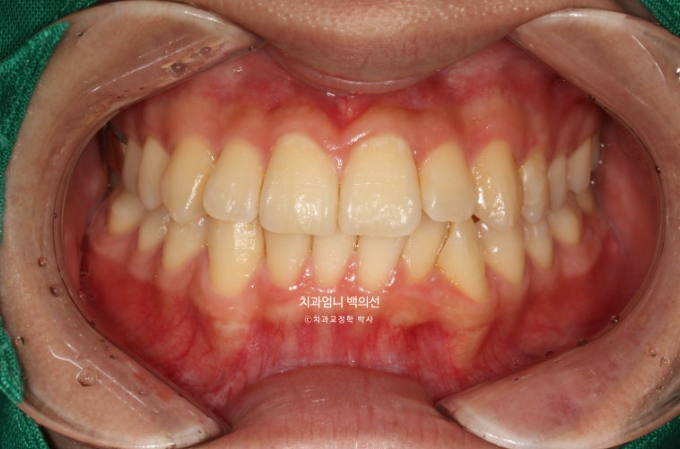

25.03

치료 후 중심선은 완벽하게 맞습니다.

1급 교합관계가 드디어 달성되었다는 전제 하에 (교합관계조차도 엉망인데 교합이 안 좋게 끝난다는 상황은 제외하겠습니다.) 사진과 같이 위아래 어금니가 약간 뜨는 현상이 생깁니다.

파란 화살표 부분이 치료 마무리 직후 논문대로 어금니 교합이 0.9mm떠있는 상태로 보시면 됩니다.

아래 사진은 2주간 교합 안정화 과정을 거쳐서 어금니가 잘 닿게된 모습입니다.